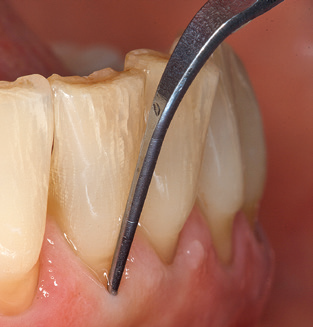

Das aktuelle Arbeitskonzept für die UPT

Die gute Ausleuchtung des Arbeitsfeldes stellt eine wesentliche Erleichterung dar. Bei dem von den Autoren genutzten System ist dies gelungen, indem ein 5facher LEDRing in das Handstück integriert wurde. Natürlich werden für dieses System unterschiedliche Arbeitsspitzen für die jeweiligen Indikationsbereiche angeboten. Eine gerade, universell einsetzbare Spitze ist das Basisinstrument zur maschinellen Instrumentierung natürlicher Zähne (Abb. 5a und b). Für schwer zugängliche Bereiche im Seitenzahnbereich werden gebogene Spitzen angeboten, die auch einen Zugang zu freiliegenden Furkationen ermöglichen (Abb. 6).

Unerlässlich für die UPT implantat prothetisch versorgter Patienten sind natürlich Arbeitsspitzen für die Reinigung von Implantatoberflächen. Der Implantatreinigungsaufsatz des hier verwendeten Systems zeichnet sich dabei durch eine spitz zulaufende sechskantige konische Form aus. Dieses Design erlaubt ein leichtes atraumatisches Eindringen in die periimplantäre Tasche und zeigt eine gute Reinigungsleistung (Abb. 7).